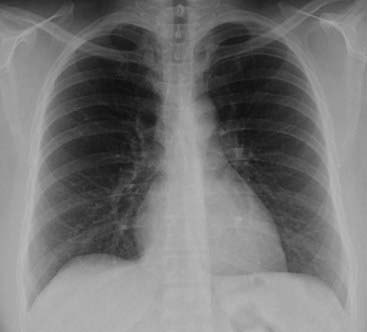

image

Figure 2-12 Counting ribs.

The posterior ribs are numbered in this photograph. Ten posterior ribs are visible above the right hemidiaphragm, an excellent inspiration. In most hospitalized patients, eight to nine visible posterior ribs in the frontal projection is an inspiration that is adequate for accurate interpretation of the image. When counting ribs, make sure you don’t miss counting the 2nd posterior rib, which frequently overlaps the 1st rib.